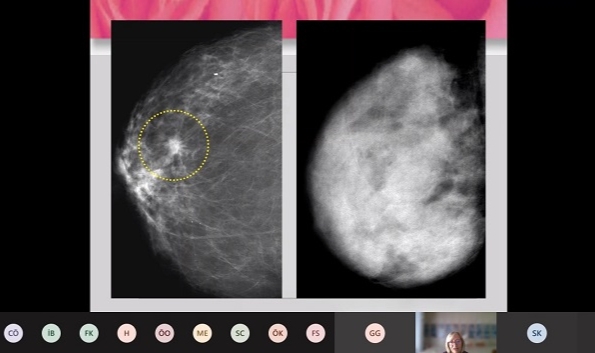

Meme kanseri tarama cihazı mamografi hakkında bilgi veren Prof. Dr. Oktay, “Etkinliği kanıtlanmış bir yöntem olan ve taramada kullanılan görüntüleme yöntemi mamografidir. Bu tarama yöntemi, çok az düzeyde x ışını kullanarak, memenin görüntüsünü elde etmektir. Özellikle günümüz teknolojilerinde dijital mamografide memeye verilen radyasyon dozu oldukça düşüktür. Bu doz günlük hayatta aldığımız zemin radyasyonuna oldukça yakındır. Bir mamografi dozu iki aylık zemin radyasyonuna neredeyse eş değerdir. Bu nedenle, mamografi cihazından çıkan radyasyonun kanser oluşumunda bir etken değildir. Momografi henüz ele gelmeyen, klinik olarak saptanma aşamasına gelmeyen lezyonu preklinik evre dediğimiz evrede ortaya koyabiliyor. Taramada amacımız; erken tanıyı ortaya çıkarmak ve doğal seyrini değiştirebilmektir. Amacımız, ölümleri azaltmaktır. Geniş olguyu içeren Uluslararası Kanser Ajansı'nın derlediği bir sonuca göre tarama ortamına davet edilen kadınlarda yüzde 23’ü, taramaya bizzat katılan kadınlar içinde de mamografi kullanıldığı takdirde yüzde 40 gibi ölüm riskinin azaldığı göstermiş" diye konuştu.

Mamografi kullanımını özellikle 40 yaşın üzerindeki kadınlara öneren Prof. Dr. Oktay, "Kadınlarda 40 yaşından sonra, 1-2 yıllık periyotlarda mamografi çekimi yaptırmayı öneriyoruz. Yıllık klinik muayene de oldukça önemlidir. Kadın doğum kontrollerinde, aile hekimleri, cerrahi kliniklerinde de yapılabilir. 40 yaşının altında ise 3 yılda bir doktor muayenesi yapılması ideal bir öneridir. Bunların yanı sıra kadınının aylık kendi memesine yaptığı muayane de oldukça önem taşır. Mamografi tek başına mükemmel bir yöntem değil. Farklı nedenlerden dolayı bazı kanserler saptanamayabilir. Yağlı meme içerisinde kitle sıkışınca cihaz kitleyi algılayamıyor ama ultrasonda bir kitle olduğu saptanabilmektedir. Bu nedenle, ek tetkik olarak ultrasonu öneriyoruz. Radyolojik taramalar, bunun yanı sıra kadının farkındalığı meme kanserinin ortaya çıkarılmasında anahtar role sahiptir." diye konuştu.